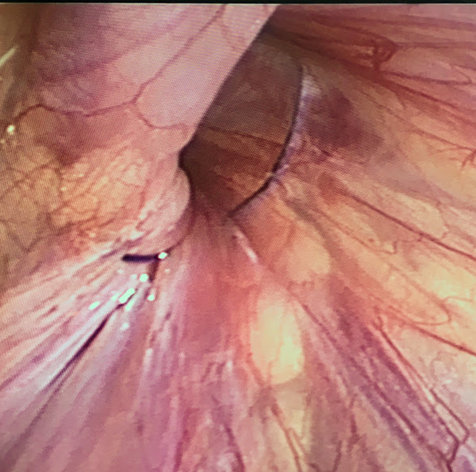

4. Rút chỉ, khâu buộc chỉ chôn dưới da. (Ảnh 3,4)

Ảnh 3: Mũi chỉ vòng qua lỗ bẹn sâu trước khi buộc